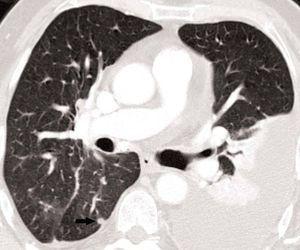

La detección de nódulos pulmonares diferentes del tumor primario es muy superior cuando el estudio está hecho con un equipo de TCMD, debido al menor espesor de corte e intervalo de reconstrucción, lo que confiere una mayor resolución espacial. Esto permite hacer reconstrucciones de proyección de máxima intensidad (MIP) que incrementan significativamente la detección de nódulos, fundamentalmente los de localización central (fig. 13)18.

Fig. 13.--Metástasis pulmonares. (A) Atelectasia del lóbulo inferior izquierdo secundaria a tumor central con nódulo pulmonar contralateral (flecha). (B) Proyección de máxima intensidad (MIP) de 15 mm al mismo nivel que muestra más nódulos (flechas).